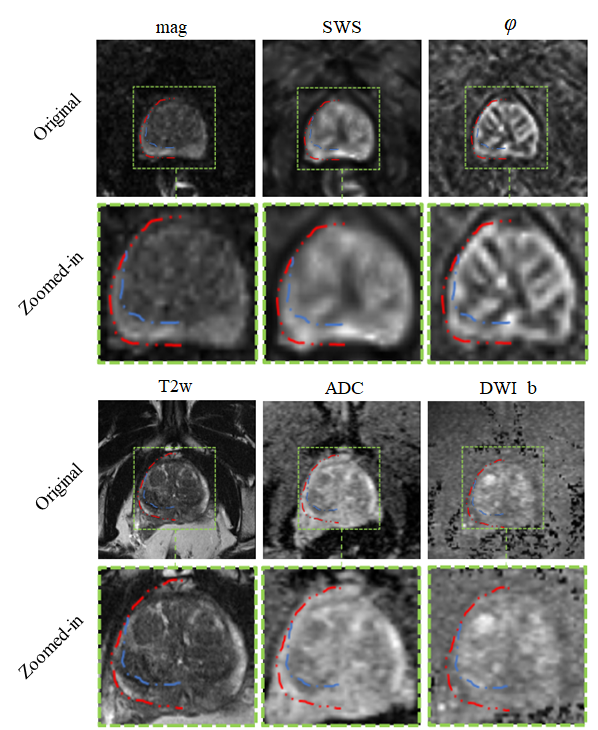

Refer to caption

Figure 1: Images illustrating the appearance of the prostate in mpMRI in a volunteer with benign prostate hyperplasia (BPH). (a) T2-weighted MRI, (b) DWI image with a b-value of 1400 s/mm2, (c) ADC map, (d) MRE magnitude signal, (e) SWS map as a surrogate marker of tissue stiffness, and (f) φ𝜑\varphi map, which signifies friction or tissue fluidity.

Our results show that IMs performed excellent across all maps and sequences with high values for DS and low values for HD. In our experiments, segmentation was most reliable when we used T2w and MRE magnitude images, which provide sufficiently rich anatomical details for automated prostate segmentation while quantitative parameter maps such as SWS, φ𝜑\varphi and ADC lack those details. Figure 9 depicts a variety of maps in a patient demonstrating that anatomy of prostate boundaries is well preserved on T2w and MRE magnitude images while it is less clearly visible on ADC, DWI_b, SWS and φ𝜑\varphi maps.

For IMs, we found no significant difference between DS of MRE and DS of MRI in PG and PZ while, in CZ, DS of MRE was higher than that of MRI. This may be explained in part by blurring due to larger slice thickness in MRI (3mm) than MRE (2mm). Furthermore, MRI slice volumes covered the entire prostate gland, the seminal vesicles and the periprostatic tissues while MRE volumes were solely focused on the prostate gland given the smaller slice thickness.